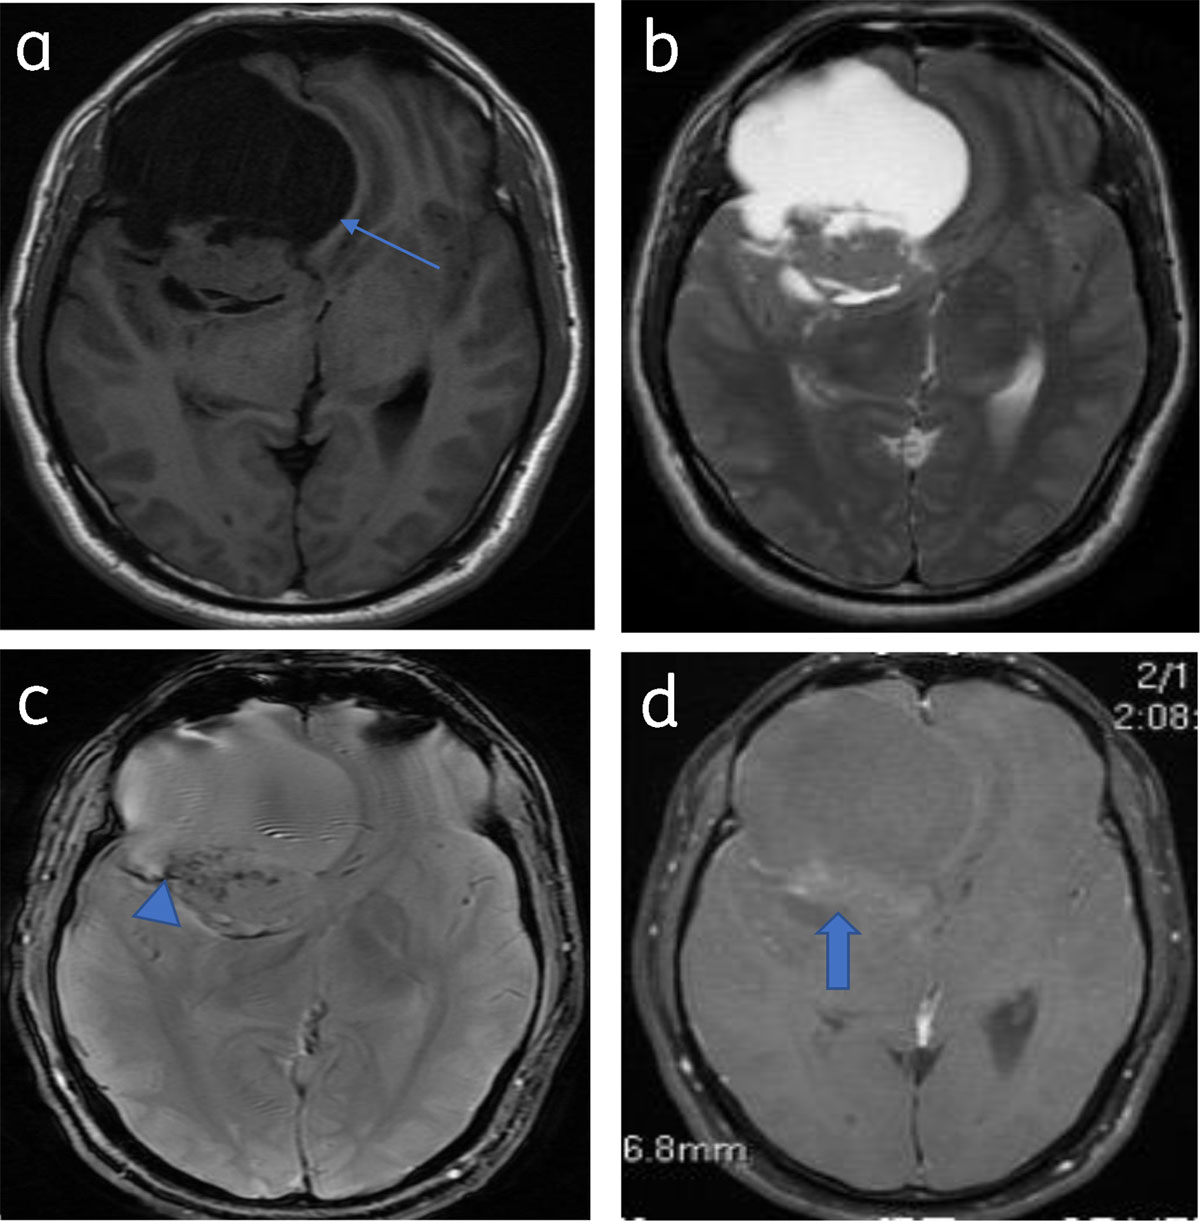

Figure 14

Predominantly cystic meningioma: Axial T1WI (a) and T2WI (b) shows right frontal meningioma with subfalcine herniation (arrow). Blooming (calcification) (arrowhead) seen on T2* image (c). Patchy enhancement of solid component (arrow) (d).